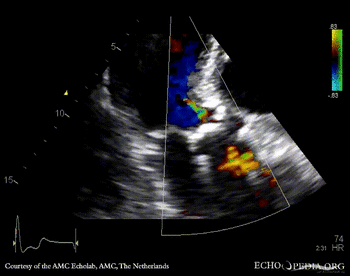

A4CH: concentric hypertrophy of left ventricle A3CH with Color Doppler: high velocity transaortic flow, mild aortic regurgitation